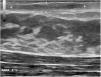

En la exploración clínica, se apreciaba un área indurada, eritematosa y elongada periareolar izquierda, dolorosa a la palpación (fig. 1). En la ecografía se visualizó en la dermis superficial una imagen longitudinal en banda hipoecogénica de 15×2,4×6mm, doppler negativa, compatible con un trayecto fistuloso (fig. 2). Con estos hallazgos la paciente fue diagnosticada de FM. Se pautó tratamiento con triamcinolona intralesional con lo que se consiguió la resolución clínica y ecográfica de la lesión. La paciente no presentó recidiva durante los siguientes 6 meses de seguimiento (fig. 3).